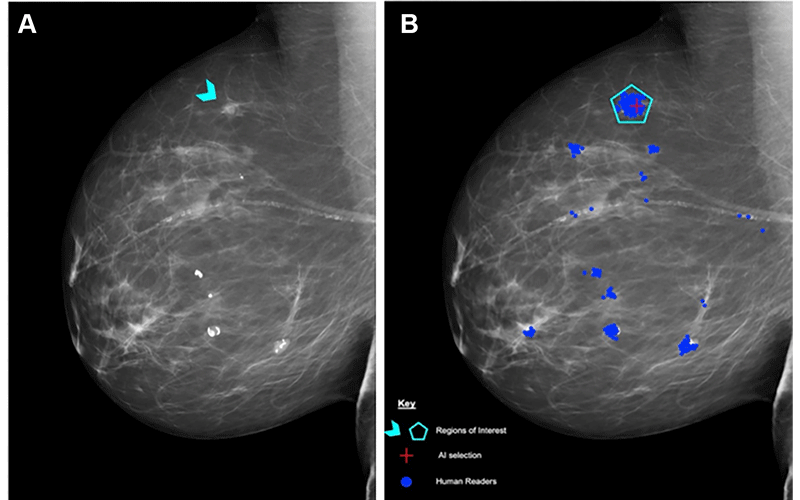

(A) Right mediolateral oblique unadulterated mammogram shows an 8-mm ill-defined mass (arrowhead), which, after biopsy, was determined to be a histologic grade 2 ductal carcinoma of no special type. (B) Mammogram shows findings by human readers (blue areas) and the Lunit INSIGHT MMG artificial intelligence (AI) algorithm (red cross). Each blue dot is a mark placed by an individual human reader on a perceived abnormality when the Personal Performance in Mammographic Screening (PERFORMS) case was read. A region of interest (pentagon) has been annotated by the PERFORMS scheme organizers and their expert radiology panel. AI has correctly marked the region of interest in the right breast for recall. Source: PERFORMS via Yan Chen.